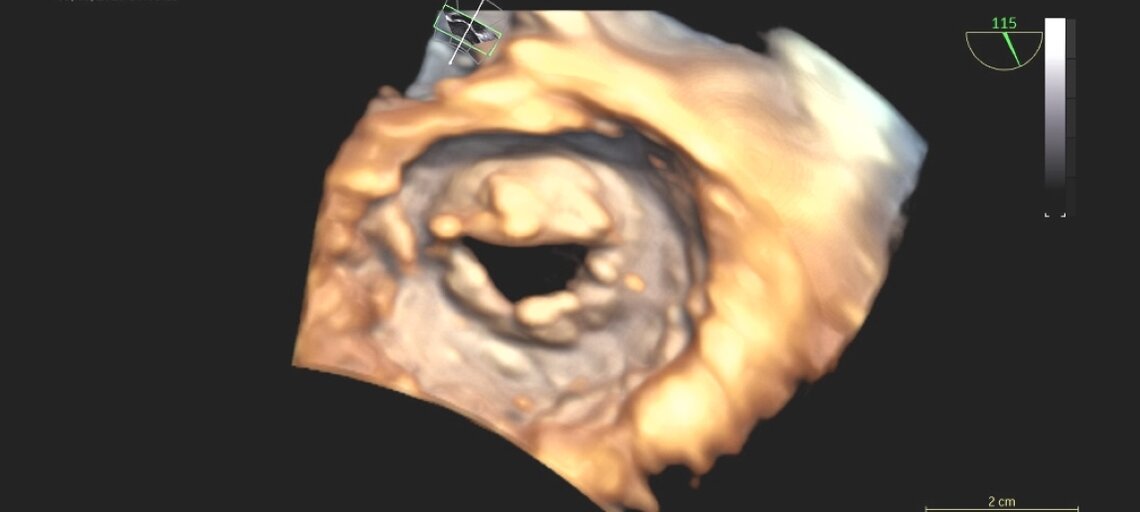

- Ecocardiogramma color-Doppler: esame fondamentale per valutare la gravità della stenosi, le cause e gli effetti su atrio sinistro e circolo polmonare.

- Ecocardiogramma transesofageo: utile per immagini più dettagliate, soprattutto in vista di un eventuale intervento di dilatazione o sostituzione valvolare.